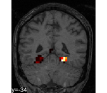

face

vs house

TV-l1

Graph-net

Social sparsity

Finally, an important aspect of the brain decoders is whether they segment well the brain regions that support the decoding. Such a question is hard to validate, yet there is evidence that TV- is a good approach [5]. Fig. 2 displays the decoder maps for the object-recognition tasks. For these tasks, we expect prediction to be driven by the functional areas of the visual cortex [27]. Indeed, the maps outline regions in known visual areas. The graph-net maps are much more scattered and less structured than the others. Conversely, the social sparsity maps are sparser and outline a smaller number of clusters.